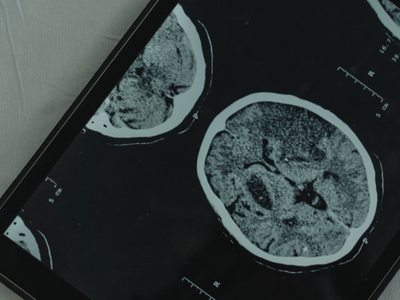

As such, it can feel devastating to be diagnosed with Parkinson’s disease – an age-related degenerative brain condition that causes parts of the brain to deteriorate.